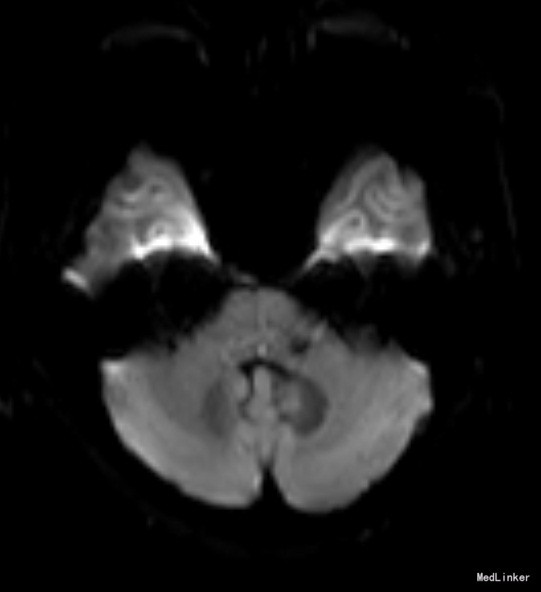

老年女性,急性起病。查体可见左眼内收受限,双眼右视时有水平眼震。影像学提示左侧桥脑背侧梗塞。与临床相符。考虑前核间性眼肌麻痹。 附上另一例前核间性眼肌麻痹头MRI,如图: